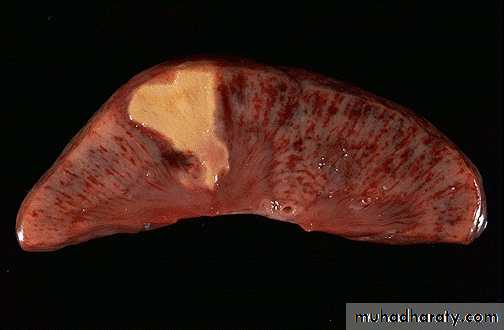

39RENAL FORM OF ATHEROSCLEROSIS

Acute form may be as infarction

Chronic form is called

AtheroscleroticNephrosclerosis or

Primary contracted

kidney